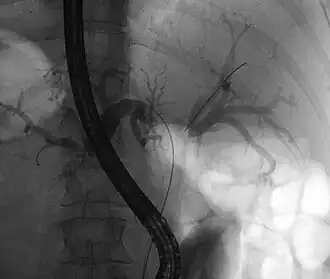

Tumeur de Klatskin lors d'une rectocolite hémorragique (absence de contraste

dans la zone de confluence).

- Cholangiographie rétrograde : identification de l'obstacle